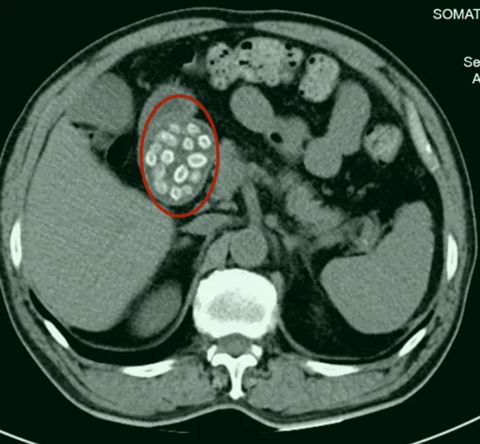

玩耍被撞后10岁男孩多器官切除,当地卫健局:医院存在问题已立案

玩耍被撞后10岁男孩被诊断有肿瘤,多器官切除 当地卫健局:医院存在问题,已立案 2023年10月26日,来自山东菏泽市成武县的小烨和他家人的命运被彻底改变了。这个原本阳光、可爱的小男孩在一次意外被撞击后,在医院检查出了腹腔内存在肿瘤,并在手术中被切除了包括十二指肠、胰腺、大部分胃和小肠等多个器官。此后便无法再像正常人一样吃饭、喝水,活着要靠长期静脉注射营养液。 一份2024年12月由第三方机构出具